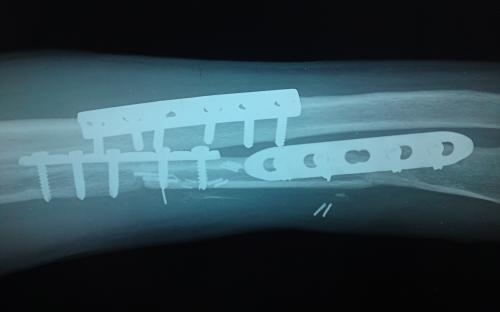

Άντρας 21 ετών υπέστη διπολικό κάταγμα της κερκίδας και κάταγμα της ωλένης, που αντιμετωπίστηκε σε περιφεριακό νοσοκομείο. 9 μήνες μετά διαπιστώθηκε ψευδάρθρωση της κερκίδας με οστικό απόλυμα 6,5 εκ. Αντιμετωπίστηκε με τη χρήση αγγειούμενης περόνης, η οποία γεφύρωσε το οστικό έλλειμμα της κερκίδας.